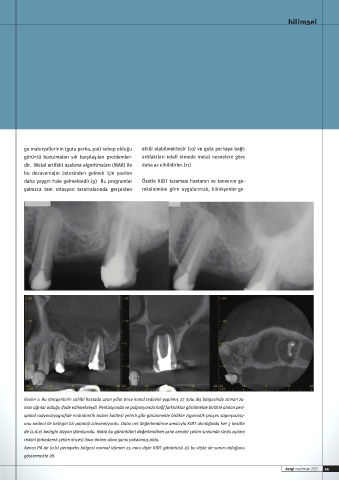

Page 45 - İDO DERGİ 182 MART- NİSAN